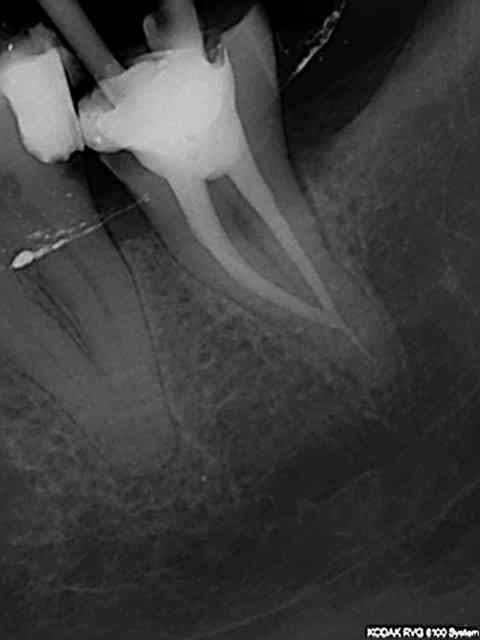

Remarque c'est pas con la tracabilité. Par exemple j'aimerais bien connaitre le nom du praticien qui a fait ce magnifique traitement endo pour savoir quel matériau il a utilisé car il a l'air d'etre très efficace; meme pas de peche !

R26 hsgjsd - Eugenol

R5 d0bnab - Eugenol